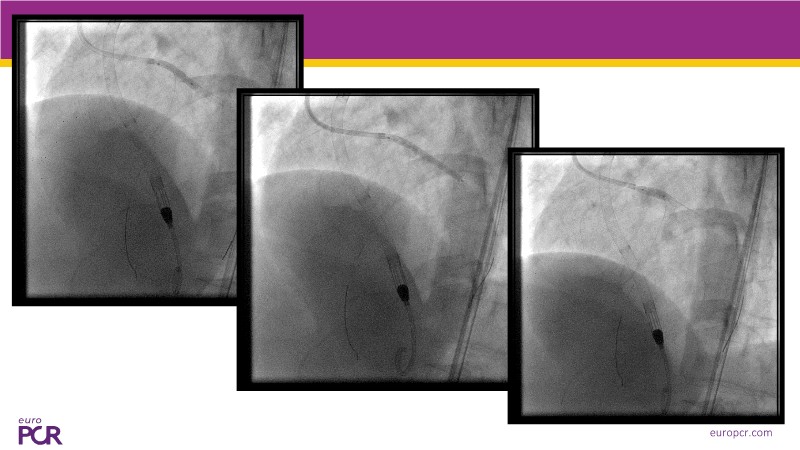

This EuroPCR 2025 session offers a comprehensive update on cardiogenic shock and high-risk PCI, featuring expert analysis of the DanGer-SHOCK and ECLS-SHOCK trials, new insights one year after DanGer-SHOCK, and practical considerations for managing PCI in patients with severely reduced LVEF. Expect to gain a deeper understanding of mechanical support strategies, survival optimisation, and the latest consensus on treating patients unsuitable for surgery.

- To learn the latest data on Impella in cardiogenic shock

- To see latest data and EAPCI consensus on high-risk PCI in patients unsuitable for surgery